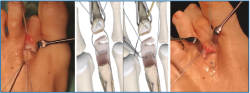

5. Pasamos las suturas por la placa plantar con ayuda de una pinza Mini-Scorpion DX® (Arthrex) (Figura 7) o de un Micro SutureLasso® (Arthrex) (Figura 8). Existen diferentes técnicas según el tipo de rotura. Para la reinserción utilizamos 2 suturas no reabsorbibles de Fiber-Wire® n.º 0 en “doble hilera” proximal y distal (Figura 9). Decidimos una u otra configuración in situ según el tipo de rotura.

Figura 7. Pase de suturas mediante pinza Mini-Scorpion®.

Figura 8. Pase de suturas con ayuda de Micro SutureLasso®.

Figura 9. Disposición de las suturas con técnica de “doble hilera”.

6. Retiramos el distractor y la agK de la falange, y realizamos 2 pequeños túneles de dorsal a plantar en la base de F1 con una broca o agK de 1,2 mm (Figura 10). Estos pueden disponerse cruzados o en paralelo. Aunque la disposición paralela pudiera teóricamente debilitar la base de F1 al ser prácticamente subcondrales, realizarlos cruzados tiene la desventaja de poder interferirse en el pase de las suturas. A través de estos túneles recuperamos las suturas preparadas en el extremo distal de la placa, de plantar a dorsal (Figura 11 y Vídeo).

7. Fijamos la osteotomía de Weil con el acortamiento metatarsal deseado y previamente establecido (se recomienda un acortamiento mínimo de 2-3 mm) (Figura 12). Con la articulación MTF perfectamente reducida y el dedo en 30° de flexión plantar, tensamos las suturas recuperadas en el dorso de F1, hasta llevar firmemente la placa plantar a su base, y anudamos (Figura 13).

Figura 10. Doble tunelización en base de F1.

Figura 11. Recuperación de las suturas de plantar a dorsal, a través de los túneles de F1.